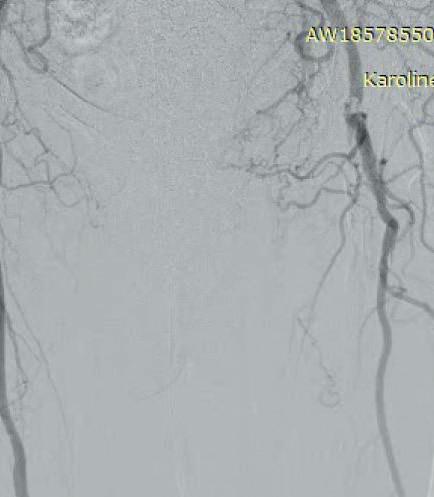

Subsequent diagnostic angiography confirmed the high grade left CFA stenosis (Figure 1) and the long SFA occlusion with diminished contrast flow below the knee. The deep femoral artery showed no significant stenosis within the first centimetres. For

In this case example, a 79-year-old man with severe claudication of the left leg was admitted to our angiology department. Cardiac risk factors included poorly controlled diabetes, renal insufficiency (GFR 27ml/min), severe obesity (body mass index [BMI] 38) and hyperlipoproteinaemia. On duplex ultrasound, a severe calcified short 90% CFA stenosis and a long 30cm occlusion of the superficial femoral artery (SFA) from the origin to popliteal artery (PA) segment one was diagnosed. The posterior tibial artery

Figure 1